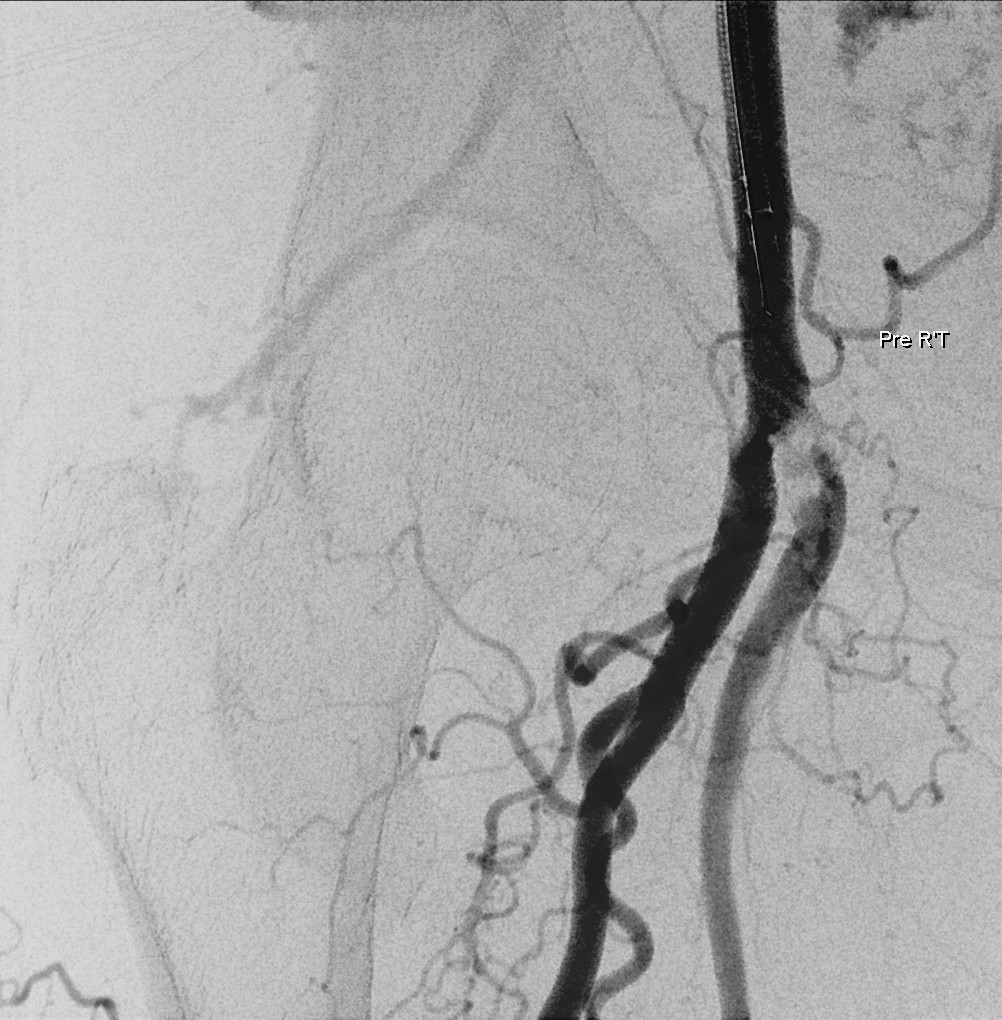

Relevant Catheterization Findings

Left femoral artery accessed under ultrasound guidance. Coronary angiography showed patent LM and LAD, mild distal LCx and OM stenosis, and irregular RCA lumen. Right lower limb angiography revealed a stumpless chronic total occlusion at the superficial femoral artery ostium with collaterals from the profunda femoris. Distal runoff was maintained through patent popliteal and anterior tibial arteries.